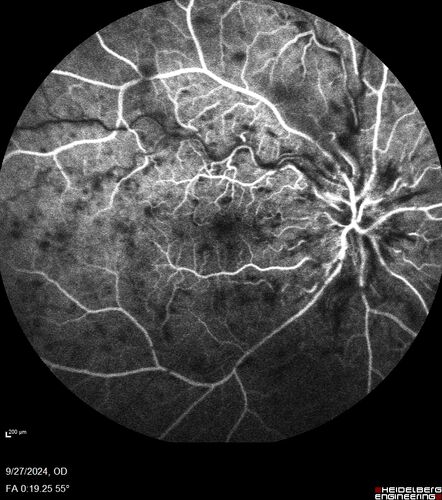

Central Retinal Vein Occlusion - Non-Ischemic - Excellent Outcome

57 year old man The right eye has had vision loss for about 3 weeks.  He woke up with vision loss.

Medical Hx: HIV . Diabetes Mellitus (since 2014). Thyroid Disease.

VA OD: sc20/160 OS: sc20/20

Treated with Avastin

VA 6 weeks later 20/32 – dry one shot.

Missed follow-up after second treatment and came  5 months later with good vision and no macular edema